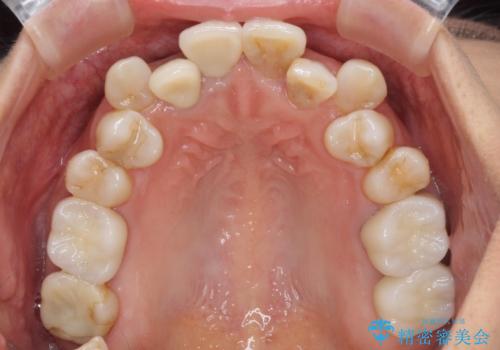

変色した前歯のオールセラミック治療

気になっていた変色が改善され、患者様には大変満足していただきました。